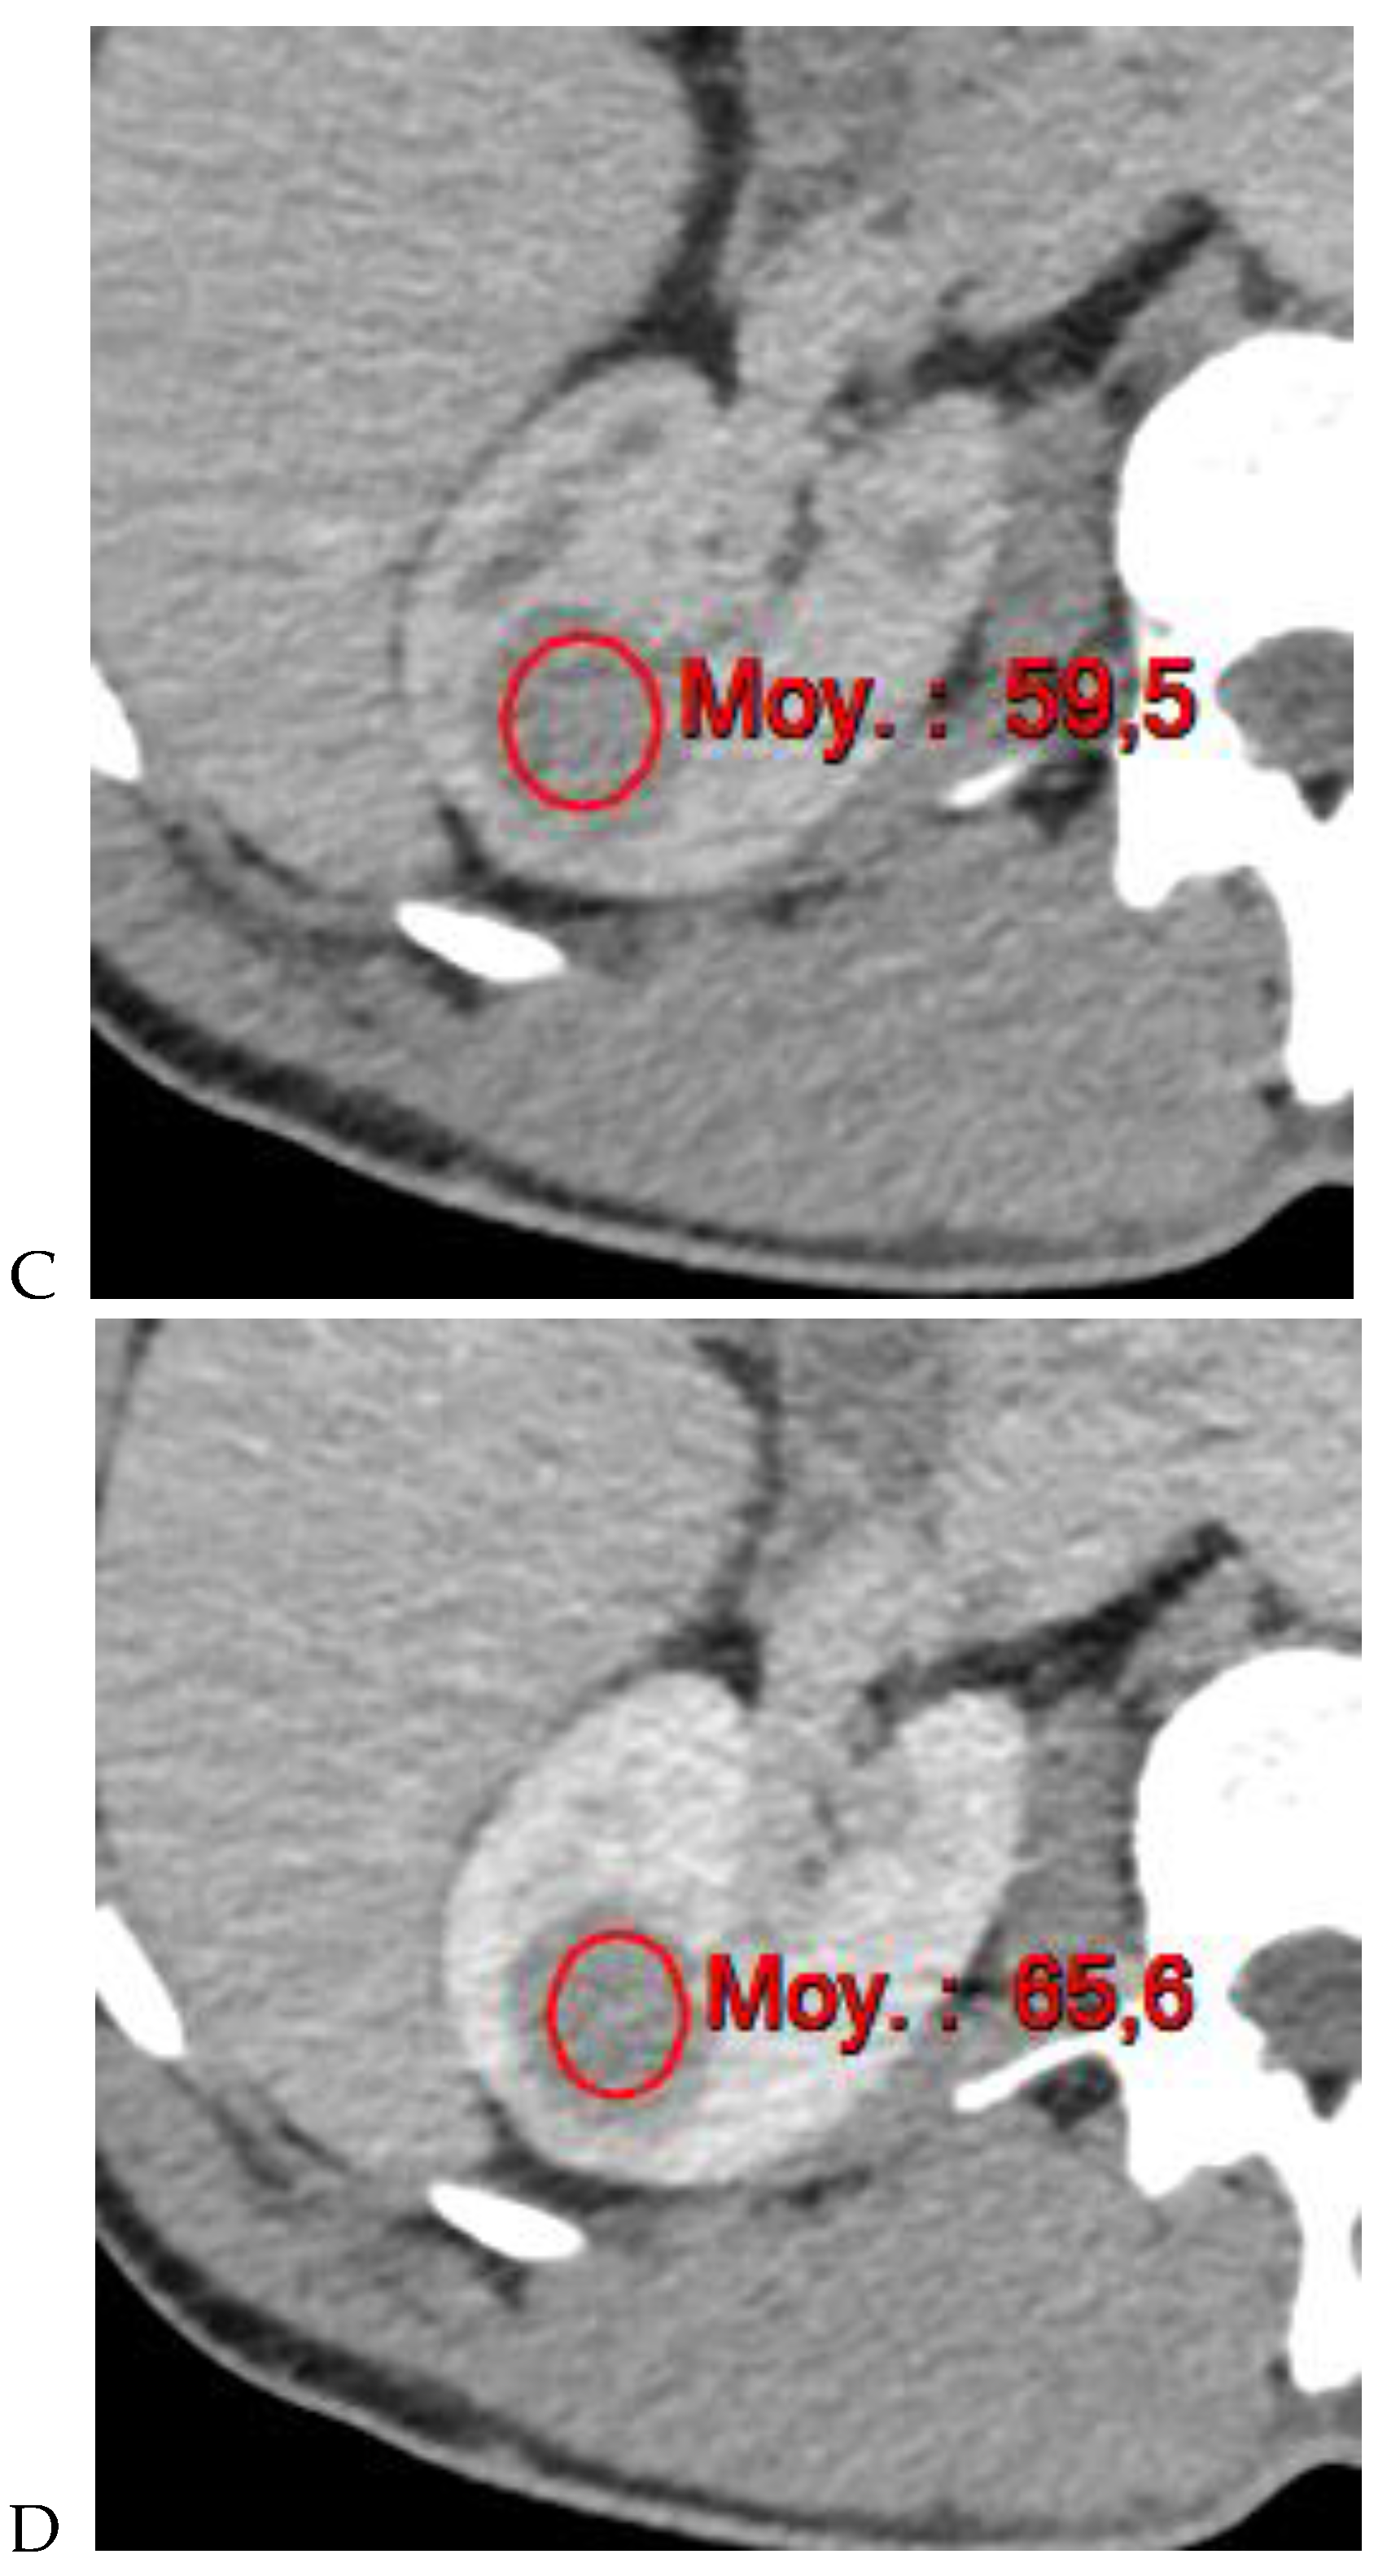

Figure 3.

CT aspect of a chromophobe renal cell carcinoma in the left kidney of a 68-year-old-woman. (A) Unenhanced image. Presence of an isodense, homogeneous solid lesion at the medium part of the left kidney. (B) It appears moderately hypervascularized on the corticomedullary phase image, with hyperdense septa. (C) There is progressive washout on the nephrographic phase image and the lesions appears hypodense relative to the renal parenchyma (C). (D) Macroscopic view of the lesion after partial nephrectomy. Courtesy of Pr S. Ferlicot, Department of Pathology, Bicêtre Hospital.

Figure 4.

Multiphasic CT enhancement of a papillary renal cell carcinoma in the middle part of the right kidney of a 63-year-old woman. (A) Mean unenhanced attenuation was 35 HU. (B) Mean corticomedullary phase attenuation was 45 HU. (C) Mean nephrographic phase attenuation was 59 HU. (D) Mean excretory phase attenuation was 65 HU.